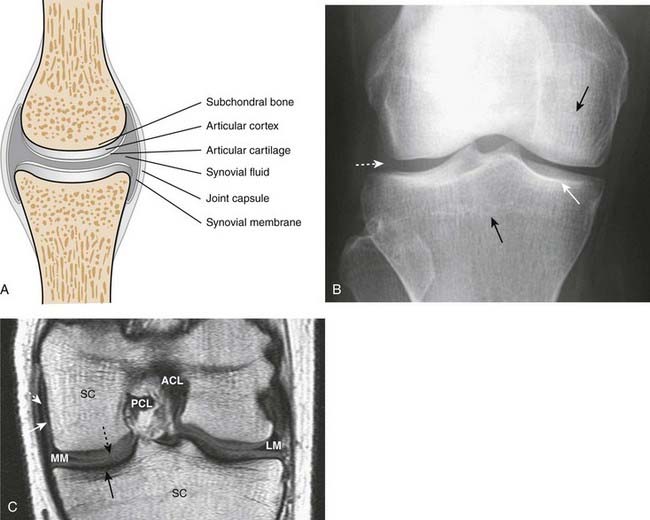

image Figure 23-1 contains a diagram of a typical synovial joint and compares the structures visualized on conventional radiographs and MRI.

image The articular cortex is the thin, white line as seen on conventional radiographs that lies within the joint capsule and is usually capped by hyaline cartilage, called the articular cartilage. The bone immediately beneath the articular cortex is called subchondral bone.

image Lining the joint capsule is the synovial membrane containing synovial fluid. The synovial membrane is frequently the earliest structure involved by an arthritis.

image Conventional radiographs will demonstrate abnormalities of the articular cortex and the subchondral bone and will provide late, indirect evidence of the integrity of the articular cartilage.

image On conventional radiographs, the synovial membrane, synovial fluid, and the articular cartilage are usually not directly visible. All, however, are visible using MRI.

Figure 23-1 Diagram, radiograph, and MRI image of a true joint.

A, A representation of a synovial joint shows the articular cortex, which corresponds to the thin, white line within the joint capsule that is usually capped by articular cartilage. The bone immediately beneath the articular cortex is called subchondral bone. Within the joint capsule is the synovial membrane and synovial fluid. B, On conventional radiographs, the articular cortex (solid white arrow) and subchondral bone (solid black arrows) are visible but the cartilage and synovial fluid are not (dotted white arrow). C, A T1-weighted coronal MRI of the knee shows the medial (MM) and lateral (LM) menisci, anterior (ACL) and posterior (PCL) cruciate ligaments, articular cartilage (dotted black arrow), joint capsule (dotted white arrow), synovial fluid (solid white arrow), and marrow in the subchondral bone (SC). The cortex of the bone (solid black arrow) produces little signal and is dark.